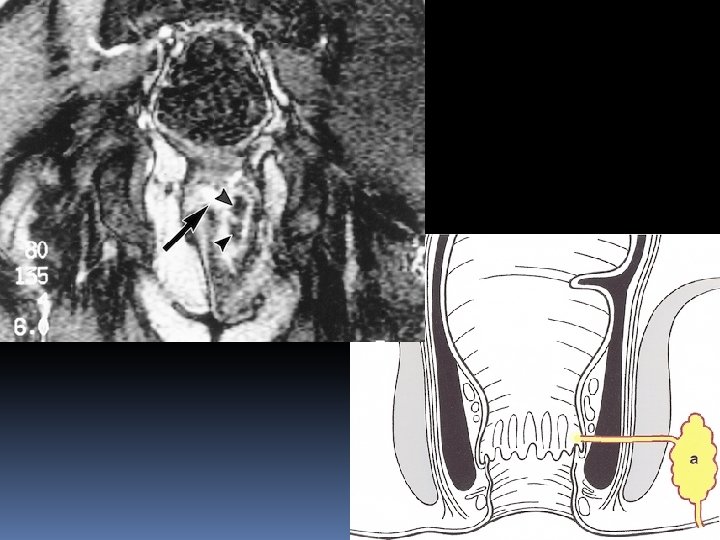

Transsphincteric fistula The defect through internal & external sphincter at 6 o’clock is clearly visible

Transsphincteric fistula at 11 o’clock